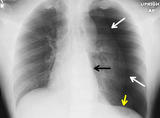

150例新生儿气胸的临床特征及预后分析

李芳 刘春翔 毛健 李娟中国医科大学附属盛京医院儿内科国际儿科学杂志, 2021,48(10) : 710-714. 《国际儿科学杂志》创刊于1974年,由国家卫生健康委员会主管,是中华医学会系列杂志。摘要目的分析不同胎龄新生儿气胸的临床特点及预后,探讨不良结局的影响因素。方法回顾性分析2012年1月至2018年12月于中国医科大学附属盛京医院第二新生儿科住院并诊断气胸的新生儿临床资料,按照胎龄分为早产组和足月组,按照结局分为存活组和死亡组,分别比较各组临床资料,多因素Logistic回归分析探讨影响气胸结局的因素。...